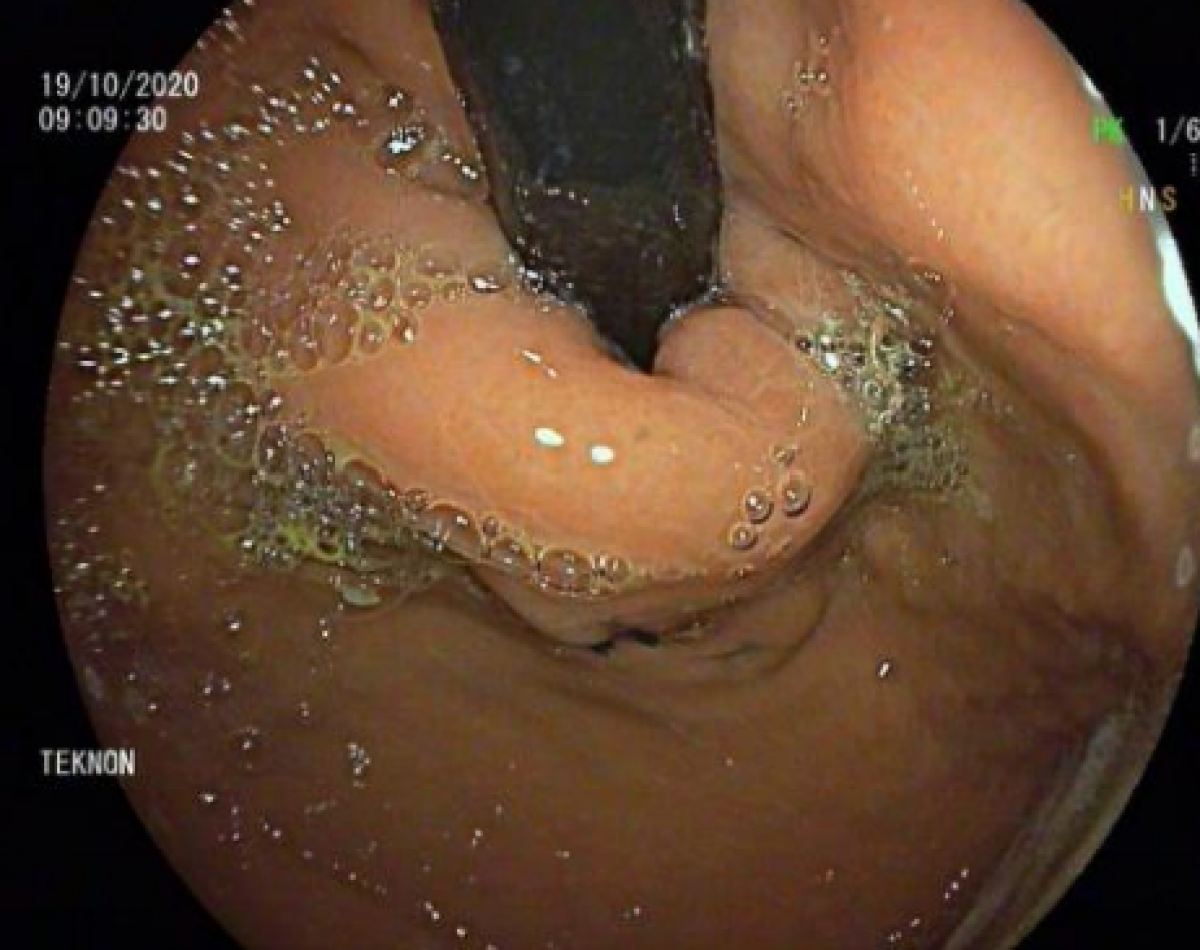

Foto Pre TIF BEC

Imatge abans de l'operació (Centre Mèdic Teknon)